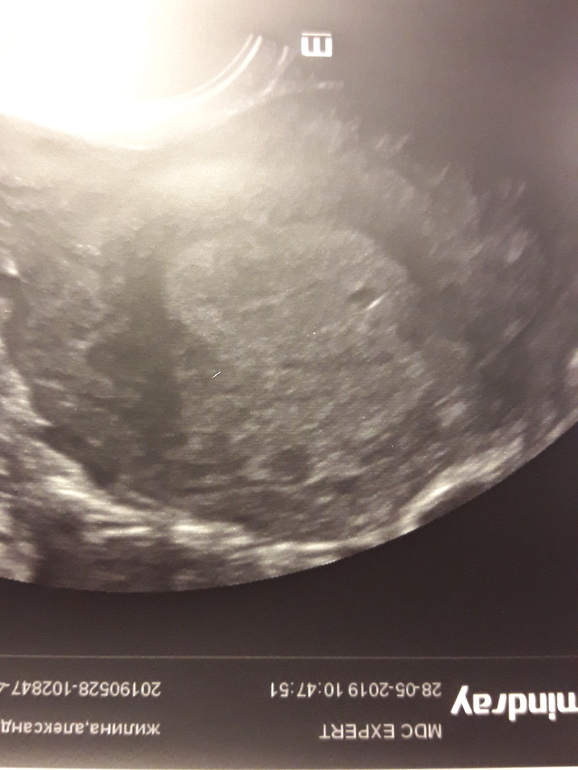

Врач прокоментировала, что по центру ПЯ, а чуть выше воздушный пузырёк при ХГЧ 874

Посмотрите пожалуйста, фото загрузилось.

Мама девочки (6 лет) Харьков

Тест сегодня может попробуйте!? Ну как вариант может и пожоже на ПЯ очень очень раннего срока. Но я не узист 🤷‍♀️ трудно оценить

Это могут быть сгустки, не очистился эндометрий. Но на всякий случай сдайте еще раз хгч. Если меньше 1, то однозначно сбой